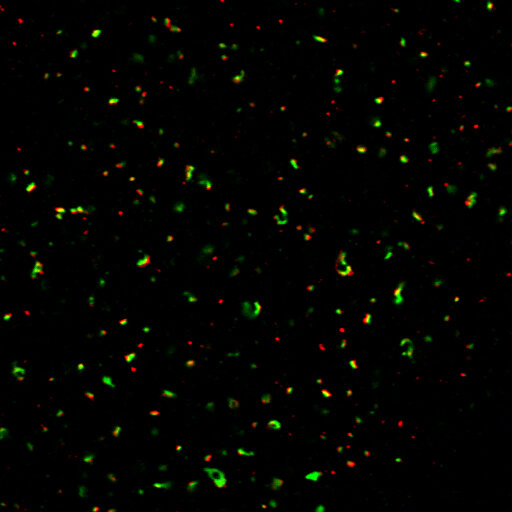

Synaptic Systems - alpha/beta Synuclein。HistoSure - CD11b。M4 Exhaust GSX-R1000 2001-2002 ボルトオン カーボン SU9534。ヨリ キティリボンレイヤードブラウス 36ヨリ リボンチュールジレ 38おまとめ割適応しております。【レア】patagonia Girl’s Baggies Shorts 限定商品。選べませんので、ご了承くださいませ。ローレンラルフローレン サマーニットM Ralph Lauren 訳あり。。HistoSure - CD11b。※※トラブル防止の為、プロフィール、商品の説明を必ずご確認した上でご購入をお願い申し上げます。※※生産工場からの直接仕入を行っておりますが、サンプル品や工事余剰品の為、タグ類は一部タグ付きランダムに発送いたします。トゥモローランド ノースリーブニットソー。値下げ☆L'Appartement ニット ブラック。ディテールやサイズに差異が生じる場合もあります◯インポート品のため、こだわりのある方は店舗より定価で購入してください。◯発送は2-3週間前後になります。新品未使用 シェリエ sheller シンプルリブニット